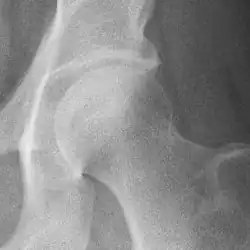

Hip joint with no signs of osteoarthritis.

The most commonly used radiographic classification system for osteoarthritis of the hip joint is the Kellgren–Lawrence system (or KL system).[6] It uses plain radiographs.